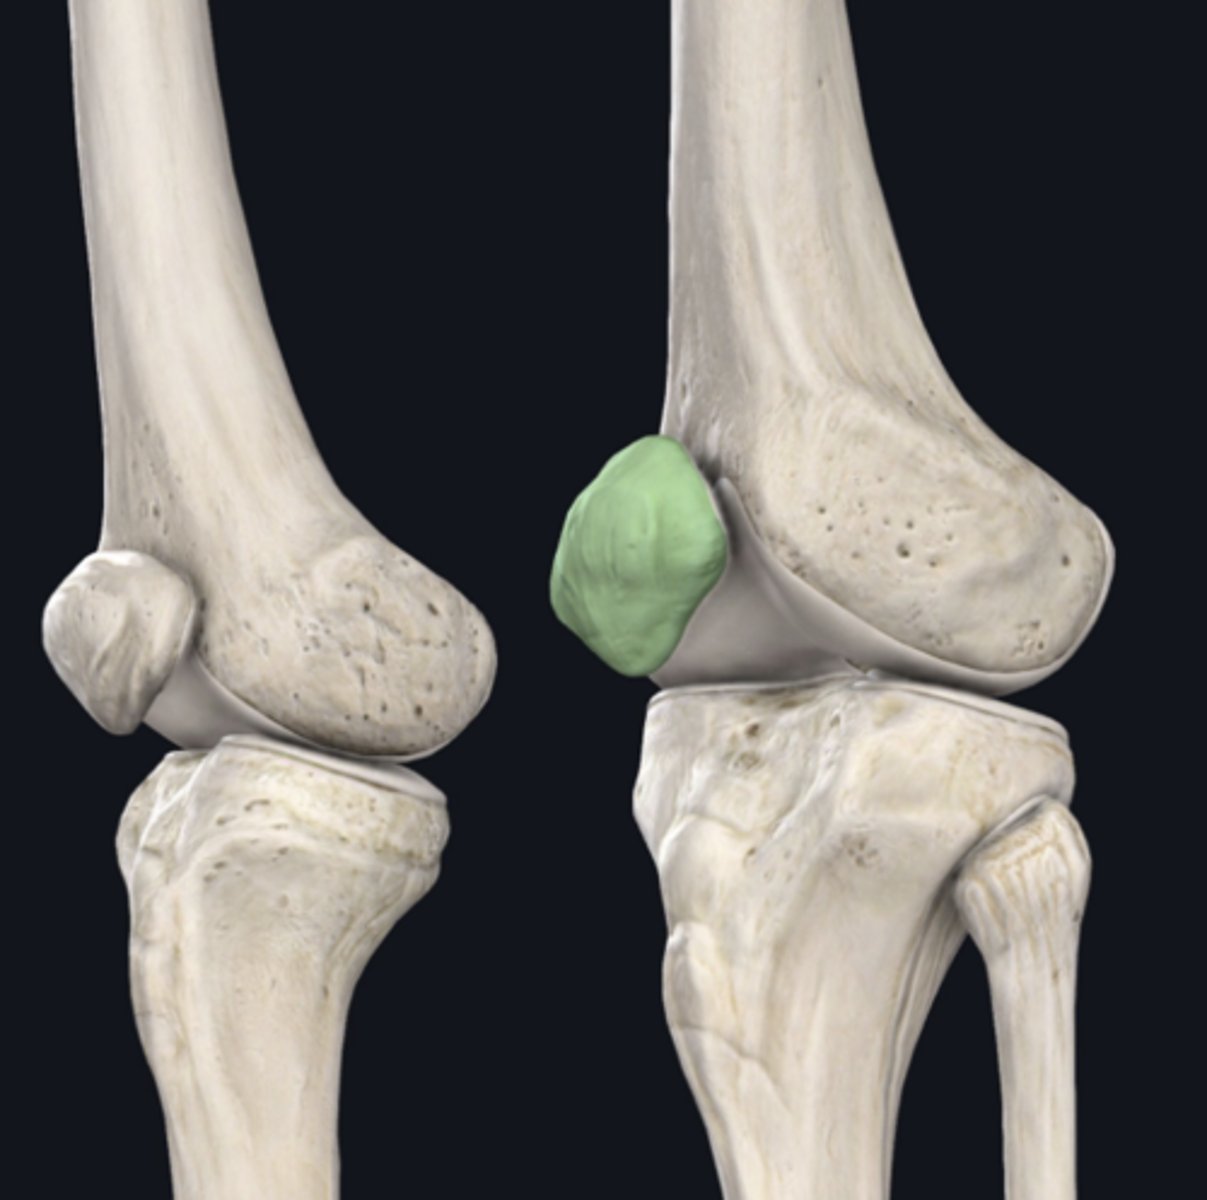

Patella

Identify the bone indicated in green. (Free response)